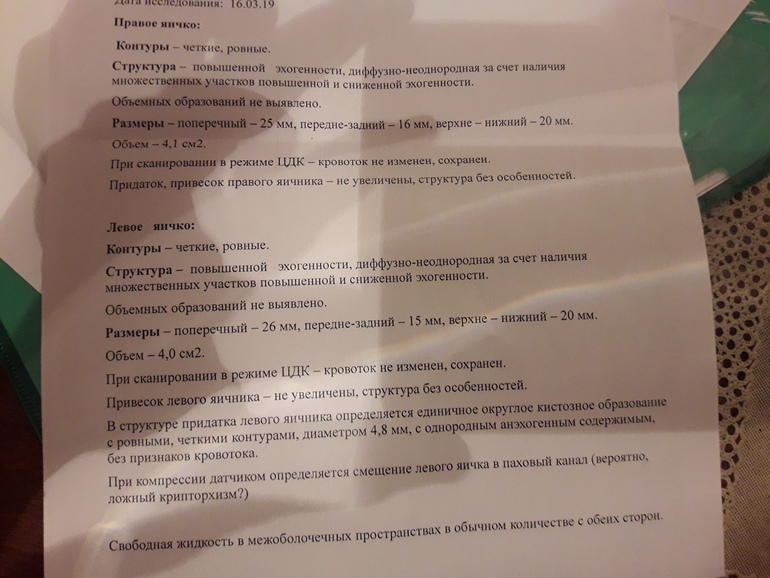

Здравствуйте.сделали узи мошенки мальчику 12 лет.показало диффузные изменения паренхимы яичек.фото прикрепляю(делали 2раза,в разных медцентрах).Подскажите,что это значит.опасаюсь самого страшного.К детскому хирургу попадем только через 3 дня,к андрологу через 4.помогите хоть немного прояснить ситуацию.(изначально обратились к урологу с проблемой задержка мочейспускания-чтобы помочиться ждет некоторое время...)спасибо.